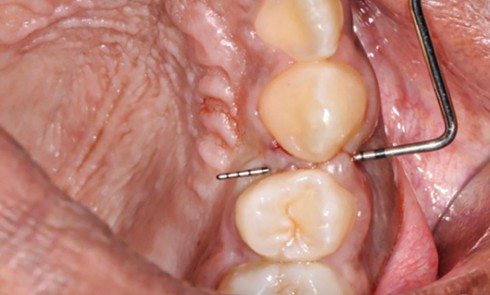

Article réservé à nos abonnés Extraction, implantation et temporisation immédiate : recycler la dent naturelle ? À propos d’un cas clinique

Les protocoles d’extraction-implantation immédiate, décrits pour la première fois en 1976 par Schulte et Heimke [1], se sont progressivement développés...